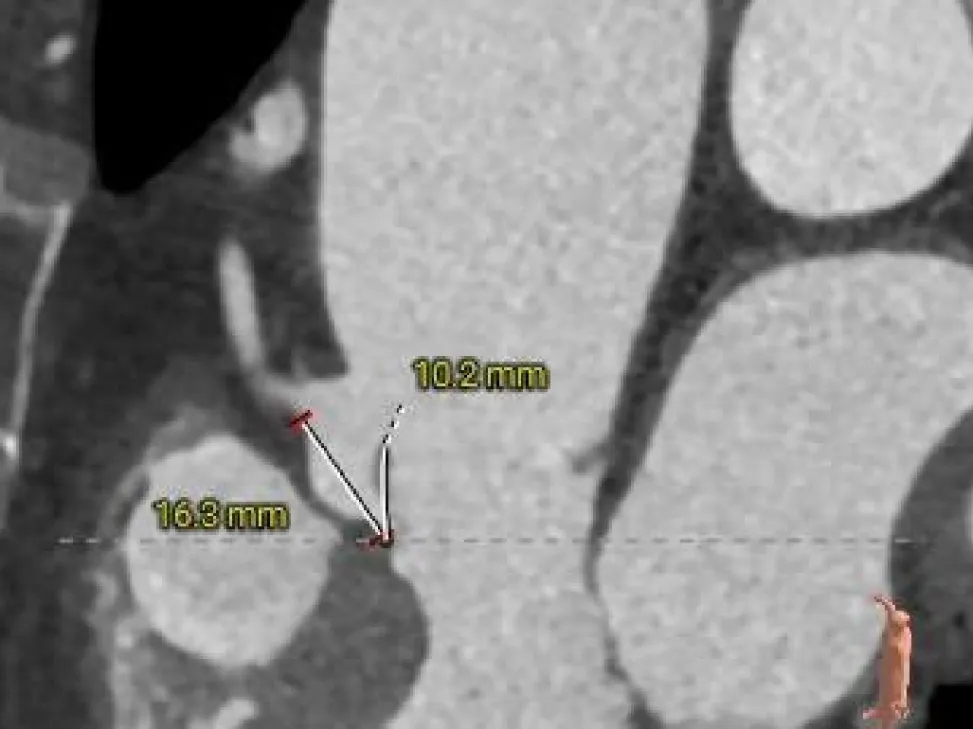

术前CT分析

三叶式主动脉瓣,瓣叶未见明显增厚及钙化,收缩期瓣环周长径约为23.6mm,流出道周长径约为21.9mm,LVOT呈收口状,舒张期瓣环周长径约为21.9mm,流出道周长径约为22.9mm;

双侧冠脉开口高度可,左窦瓣叶切线测量距离<冠脉开口下缘到根部距离;

瓣环水平夹角50°,非横位心,升主动脉未见扩张;

主动脉根部测量

Annulus

23.6mm

LVOT

21.9mm

瓣上结构测量

Annulus:

24.5mm

瓣上4mm:

24.9mm

瓣上6mm:

26.6mm

瓣上8mm:

27.1mm

瓣上10mm:

27.5mm

未见明显钙化

冠脉风险评估